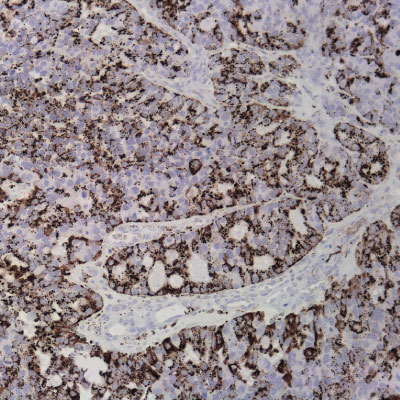

Immunohistochemistry integrates a set of methodologies that use antibodies as specific reagents capable of identifying and establishing specific links with tissue constituents that function as antigens.

Established bindings can be visualized under microscopic observation, due to the labeling of antibodies that cause color development whenever antigen-antibody complexes are formed.

​Vitro Turkey Diagnostics, through its exclusive representation of Master Diagnostica in Turkey, sells antibodies and equipment for immunohistochemical diagnosis (IHC), offering a wide panel of primary antibodies (more than 300 references), as well as universal and high-quality detection systems. sensitivity, based on micropolymer technology for in vitro diagnostics.

With the main objective of providing innovative and top quality antibodies for immunohistochemical diagnosis, we work daily to be informed of the problems and needs of the market, in order to be able to offer our customers the most innovative antibodies with total quality assurance.

Top quality antibodies for immunohistochemical diagnosis. More than 300 references.

Universal and high-quality detection systems. Sensitivity, based on micropolymer technology for in vitro diagnostics.